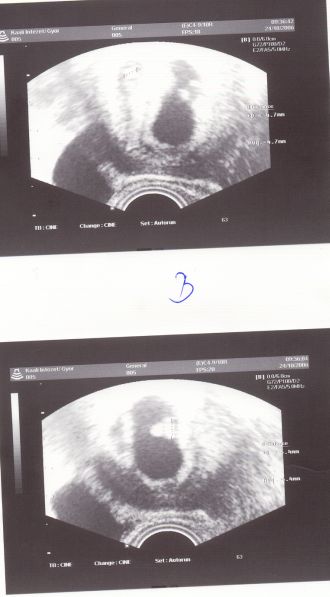

Mi volt uh-n???